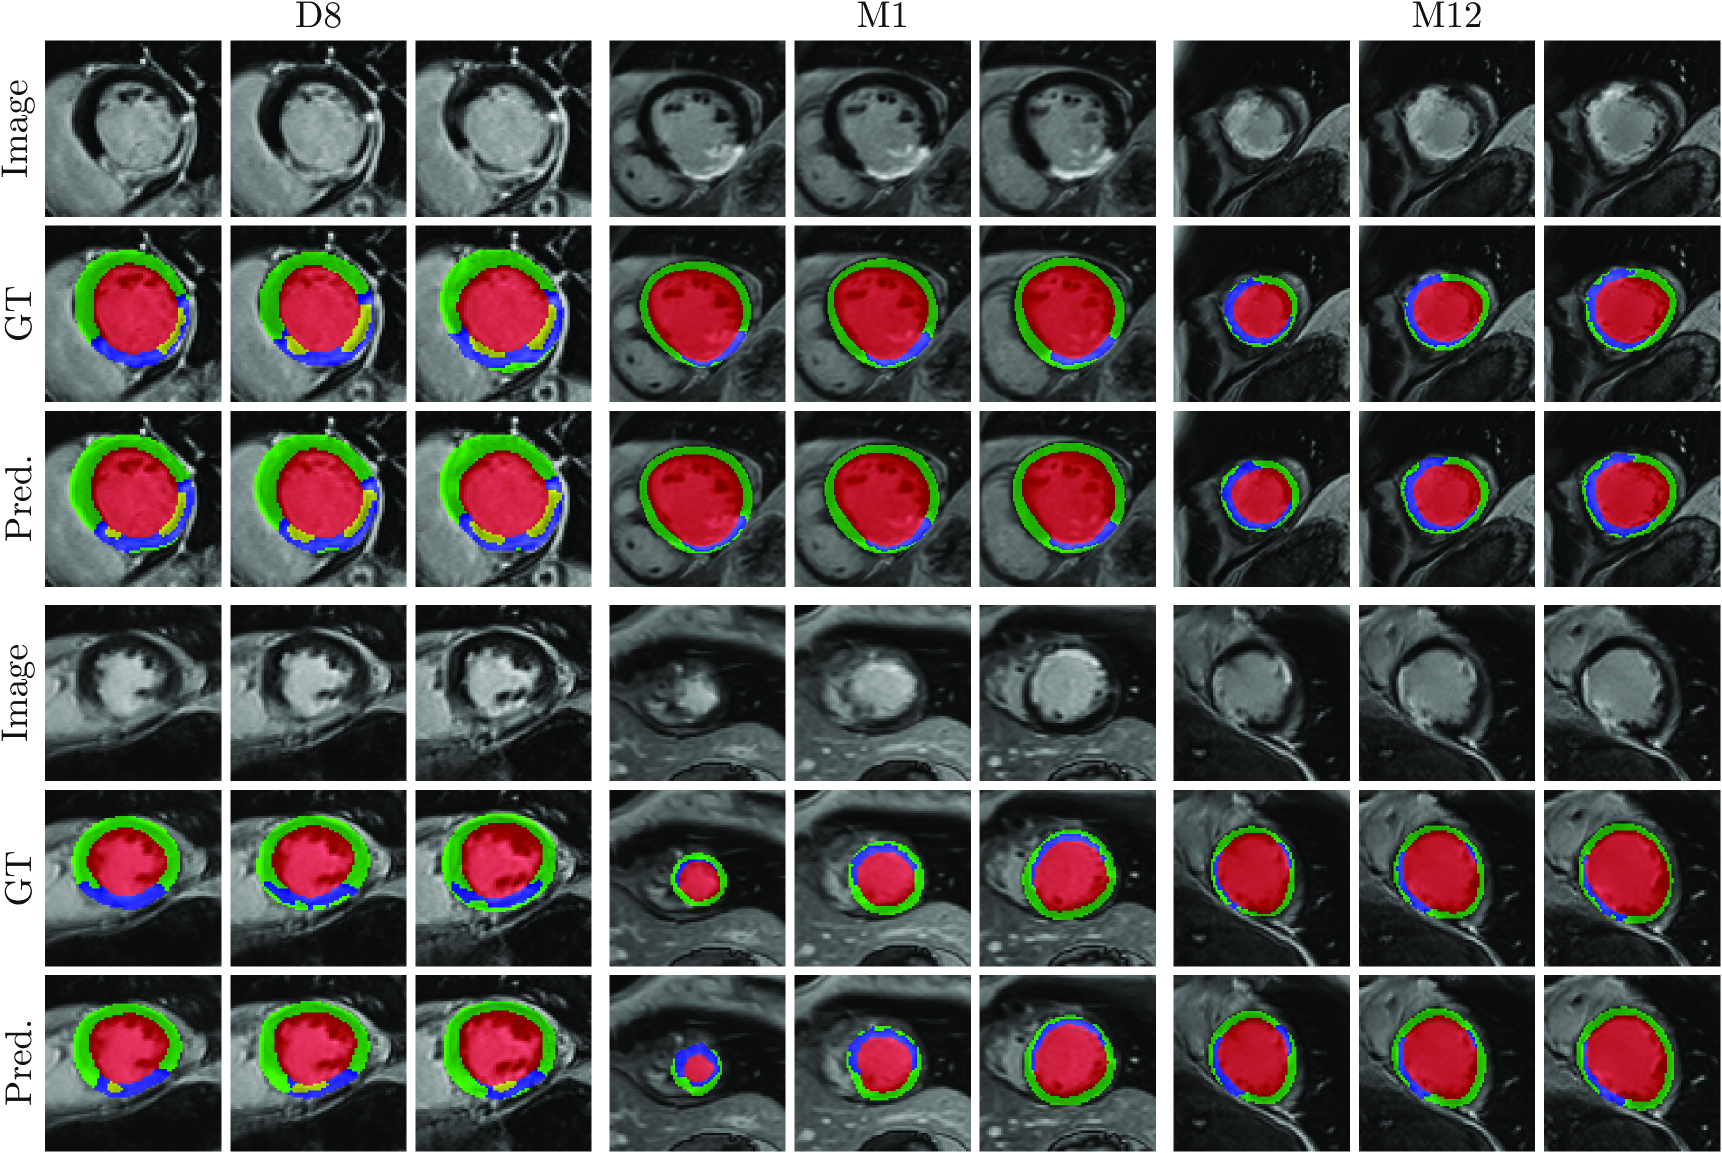

Refer to caption

Figure 6: Qualitative results of CaRe-CNN on the test set. Columns refer to three consecutive slices of LGE MR scans of patients after MI for each subgroup: D8 (col. 1-3), M1 (col. 4-6) and M12 (7-9). Rows refer to scans of two separate patients and show the image (rows 1, 3) and prediction of CaRe-CNN (rows 2, 4). Ground truth is not available for the test set.

The qualitative evaluation of our CaRe-CNN is performed by visually inspecting the predictions. As ground truth segmentations for the test set data are hidden, we also present qualitative results of CaRe-CNN trained on 2/3232/32 / 3 and validated on 1/3131/31 / 3 of the actual training data for the MYOSAIQ challenge in Fig. 5 to allow a comparison of our predictions to the ground truth. Additionally, we provide qualitative results of our final method submitted to the challenge on the test set in Fig. 6, however, without publicly available ground truth segmentations, the predictions are only compared to the respective input images. Both figures show three consecutive slices of two MR scans of patients after acute MI per subgroup (D8, M1, M12).

The qualitative results on the validation set in Fig. 5 confirm that most label predictions are very close to the ground truth. On closer inspection, however, some differences can be spotted. For example, one of the two MVO regions is predicted in one additional consecutive slice in contrast to the ground truth (D8, top), while the MIT label is overpredicted close to the apex (M1, bottom). Also, an MVO label prediction for a patient without MVO is visible (D8, bottom). Nevertheless, many regions are predicted correctly, most notably even for data where the wall is in parts only two to three voxels thick (M12, bottom). On the test set in Fig. 5, qualitative results can only be compared to the LGE MR image. Overall, the label predictions appear to be realistic which is supported by our quantitative evaluation, however, further confirmation needs to be performed by an expert.